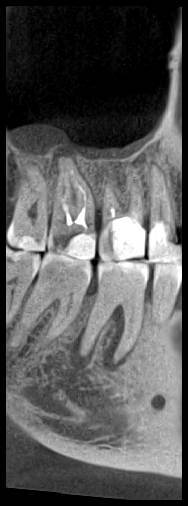

КТ от 04.03.2024

69273_3.jpg.f56a31dc1d8d53085767a9a52915128c.jpg69273_4.jpg.f9ec255bedbdb9fde8159318d3cb1fd9.jpg69273_5.jpg.36a7a942d403dd2eb062e5a4b2b58a52.jpg69273_6.jpg.492d3fbca3808fbdf58c86056b2fe0c3.jpg69273_7.jpg.f9bfdd5d593504dc7bd3710ece18aa4f.jpg69273_8.jpg.853e2342e6f2329a2e89c8939c2aad6f.jpg69273_11.jpg.e495813d50bf007f7165bf5f5dfec4b3.jpg69273_12.jpg.49b3cf66b4dd26b5cd68a91b2684e402.jpg69273_13.jpg.5d61b621b8e8b2c473ad6a8aca42502d.jpg

Добрый день! В данный момент прохожу лечение 46 зуба. Улучшений нет, поэтому возникли сомнения в тактике лечения выбранной моим стоматологом.

Предоставил доктору КТ от 04.03.2024(приложено ниже). Доктор посетовала на то, что в 3D не очень умеет, только панорамные снимки. Новый снимок, или КТ не предложила сделать. Вскрыла полость зуба, прочистила каналы, и заложила "Пульпосептин"(с ее слов), закрыв временной пломбой. Пломба была странная шершавая, похожая на высохшую зубную пасту, и за два дня наполовину "сточилась".

Лекарство было извлечено, и каналы запломбированы гуттаперчей. Доктор предупредила, что зуб будет болеть, и прийти я должен после того, как зуб "успокоится", болевые ощущения пропадут. На третий день десна под зубом вспухла, и начала сочиться сукровица. Я решил сделать новое КТ(28.05.2024), и с результатом сходить в другие клиники для консультации. В первой мне сказали, что доктор не должна была начинать лечение, потому, что зуб идет под удаление. Во второй клинике, что попытаться вылечить можно, но изначально были допущены ошибки в лечении, и надо переделывать.

Что-то можно сделать с 46 зубом для сохранения, или он должен быть удален?